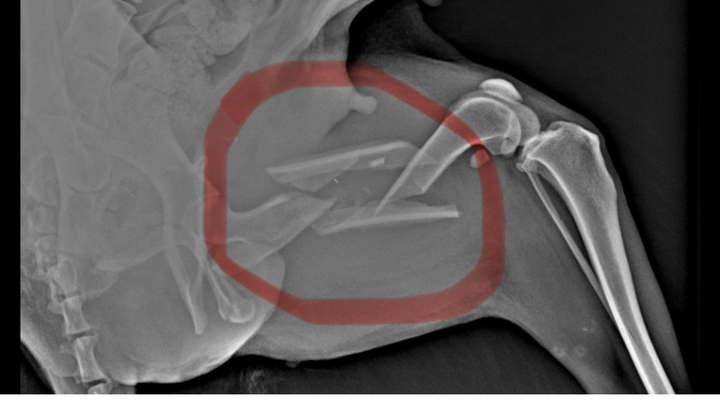

Hallo, ich bin Bianca und das ist Mina. Ich habe diese Hündin angefahren im Straßenrand gefunden, nach Untersuchung und Röntgen ein doppelter Bruch im Oberen Hinterbein.